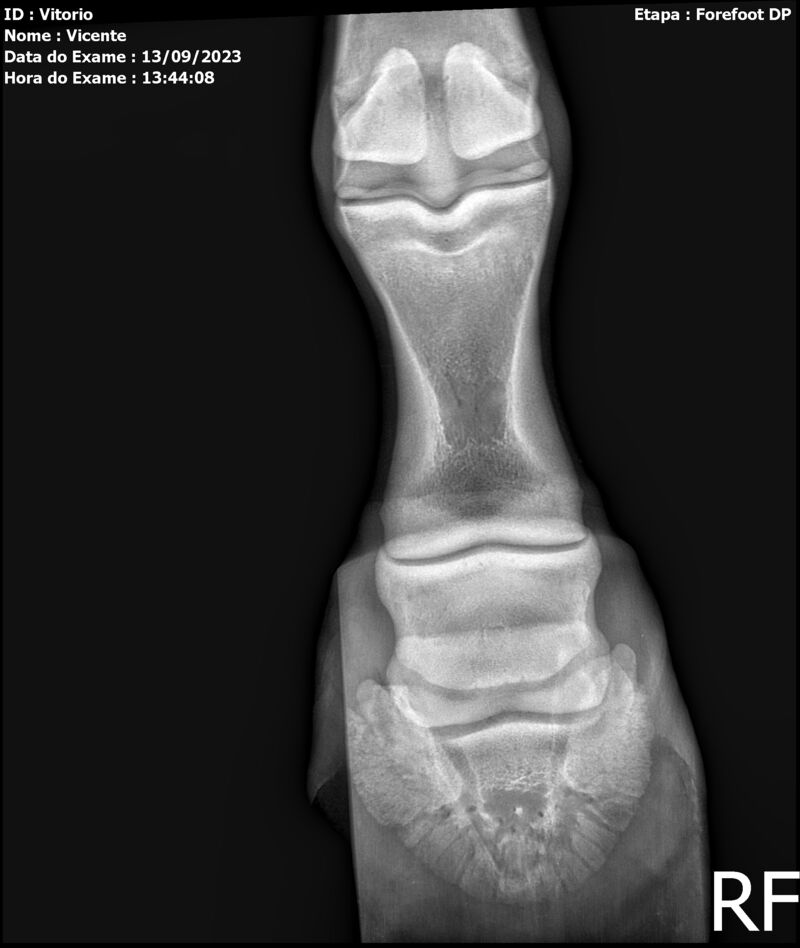

LOTE 13

THUNDER ZC

Raça: BRASILEIRO DE HIPISMO

Sexo: MACHO - POTRO

Nascimento: 17/09/2022

Altura Aproximada: 1,54

Pel.: CASTANHO

Registro: EM AND

Vend.: VICENTE CONTE

Local : PORTO FELIZ/SP